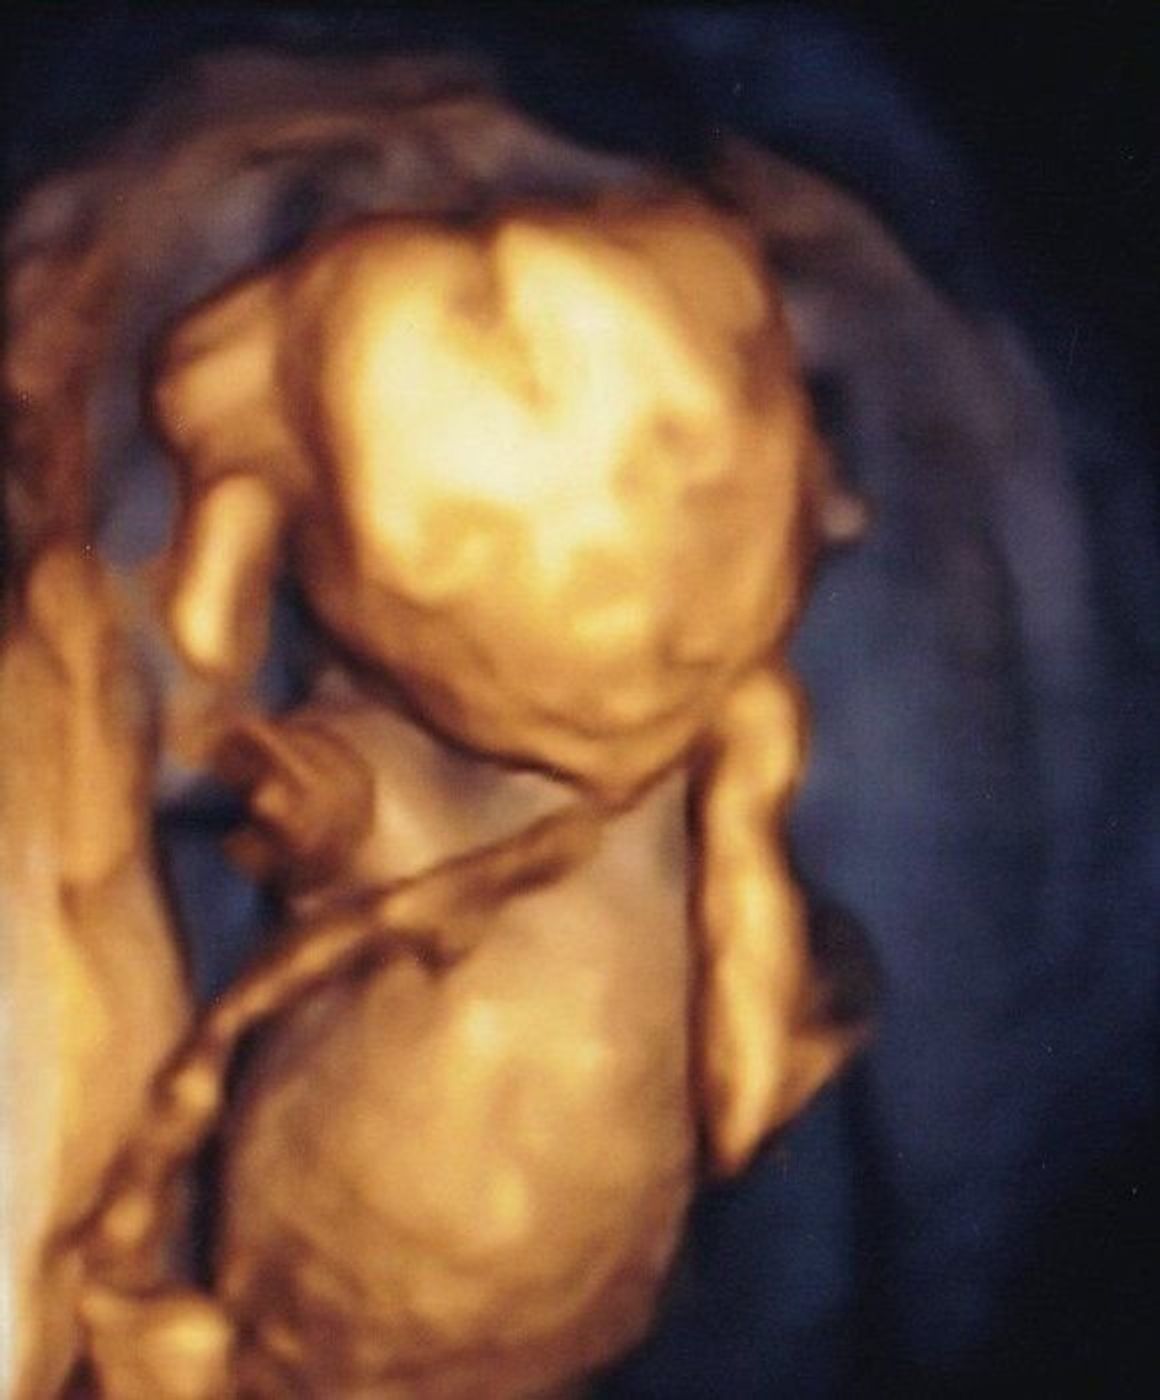

18 週 エコー 女の子- 18 週 エコー 女の子 突起 物 こんばんは 現在妻が妊娠18週なのですが 前回の検診で性別がまだ判断 妊娠 教えて Goo エコーでの性別判断 女の子でしょうか Okwave妊娠週 18w0d BPD (頭の幅) 453ミリ AC (腹部周囲長) 1292ミリ FL (大腿骨長) 251ミリ 体重は225グラム、頭からお尻まで13センチで足を伸ばせばセンチ弱とのこと。 順調だそうです♪ 『ぜひとも性別をお願いします! 』で、エコー開始数秒で写真の通り男の子と

妊娠30週目の女の子のエコー写真 女の子を見分けるのは足の間の突起物が無いかコーヒー豆が見えるか! 女の子の性別判定はいつから可能? 女の子の性別判定はいつから可能なのでしょうか? 男の子も女の子も外性器がしっかりと形成され、 性別判定 妊娠17週のエコー写真はどんな風に映るのか、気になるママ・パパのために先輩ママ達の妊娠17週当時のエコー写真とエピソードを多数紹介します。 今日は横向いてたから性別わからないけど、男の子でも女の子でもとりあえず楽しみ〜♡ 年09月18日妊娠18週3日(18w3d)の超音波(エコー)写真 o 性別も女の子だろうねーとの事! 健康に産まれてくれればいい! と一番に思ってますが、理想としては 最初の子は女の子がいいねと パパと話してたので2人でニマニマしてました^^

妊娠18週 性別は女の子に判明 エコー画像を大公開 初めての妊娠出産 育児をぜーんぶ海外で ぽんはのブログ

妊娠 18週目 性別判明 3d写真 イギリス生活 国際結婚 言語習得 海外ドラマ 映画 番組レビュー 留学 海外で出産と子育て 世界一周旅行など